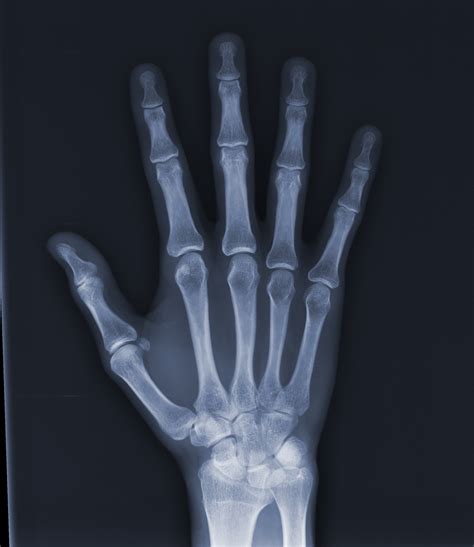

La edad cronológica no siempre permite valorar el desarrollo y la maduración somática del paciente, por lo que se recurre a determinar la edad biológica, que se calcula a partir de la edad ósea, dental y morfológica o del momento de la maduración sexual. Por lo general, la edad ósea, se valora con una radiografía de la mano, que se considera el reloj biológico. La madurez ósea se determina hasta el noveno año de vida por el grado de mineralización de los huesos de la muñeca (carpo) y posteriormente, por el desarrollo de los huesos metacarpianos y falanges.

Edad Biológica y Radiografía de la Mano

La interpretación de la radiografía de la mano se basa en diversos factores de desarrollo y maduración, que aparecen en forma regular y secuencial durante los mismos. En ortopedia maxilar se ha utilizado el análisis de Bjork, que divide el proceso de maduración de los huesos de la mano en 9 estadíos evolutivos entre el noveno y los 17 años de edad. Las características de osificación se detectan a nivel de las falanges, huesos del carpo y radio.

Los estados de crecimiento de los dedos se valoran según la relación entre la epífisis y la diáfisis. Se distinguen tres Estadíos de Osificación de las Falanges.

- Primer estadío: la diáfisis tiene la misma anchura que la epífisis.

- Segundo estadío: estadío de capuchón, donde la diáfisis rodea a la epífisis a modo de capuchón.

- Tercer estadío: estadío de U (U=unidad) donde la diáfisis se osifica con la epífisis.

Los dedos se denominan con las cifras 1 a 5 a partir del pulgar. El primer estadío comienza aproximadamente 3 años antes del brote de crecimiento puberal. El segundo estadio de osificación coincide con el brote máximo de crecimiento puberal, y se corresponde con el quinto estadio de maduración del esqueleto de la mano. El tercer estadío de osificación significa la terminación del brote de crecimiento puberal y se corresponde con el sexto, séptimo, octavo y noveno estadios de maduración de la mano.

Según el análisis de la radiografía de mano de Bjork, Grave y Brown, encontramos los siguientes estadios de maduración:

Estadios de Maduración Según Bjork, Grave y Brown

- Primer estadio de maduración: La diáfisis de la falange proximal del dedo del dedo índice (PP2), muestra la misma anchura que la epífisis. (=). Este estadio comienza aproximadamente 3 años antes del brote de crecimiento puberal.

- Segundo estadio de maduración: La diáfisis de la segunda falange del dedo medio (MP3) muestra la misma anchura que la epífisis. (=).

- Tercer estadio de maduración: -(Pisi): Osificación visible del hueso pisiforme. -(H1): Osificación de la apófisis uniforme del ganchoso. - (R): Anchura equivalente de la diáfisis y epífisis del R.

- Cuarto estadio de maduración: -(S): inicio de la mineralización del sesamoideo. - (H2): osificación avanzada de la ap. unc. del ganchoso. Este estadio se alcanza poco antes o al inicio del brote de crecimiento puberal.

- Quinto estadio de maduración: - (MP3 cap.): la diáfisis rodea a modo de capuchón a la epífisis, a nivel de la segunda falange del dedo medio. - (PP1 cap.): en la falange proximal del pulgar. - (R cap.): en el Radio. Este estadio de osificación coincide con el brote máximo de crecimiento puberal.

- Sexto estadio de maduración: - (DP3 u.): Fusión visible de la diáfisis y epífisis de la falange distal del dedo medio. Al alcanzarse este estadio evolutivo, termina el brote de crecimiento puberal.

- Séptimo estadio de maduración: - (PP3 u.): Fusión visible de la diáfisis y epífisis de la falange proximal del dedo medio.

- Octavo estadio de maduración: - (MP3 u.): Fusión visible de la diáfisis y epífisis de la segunda falange del dedo medio.

- Noveno estadio de maduración: - (R u.): Osificación completa de la diáfisis y epífisis del Radio. Al llegar a este estadio, termina la osificación de todos los huesos de la mano y, al mismo tiempo, el crecimiento óseo.